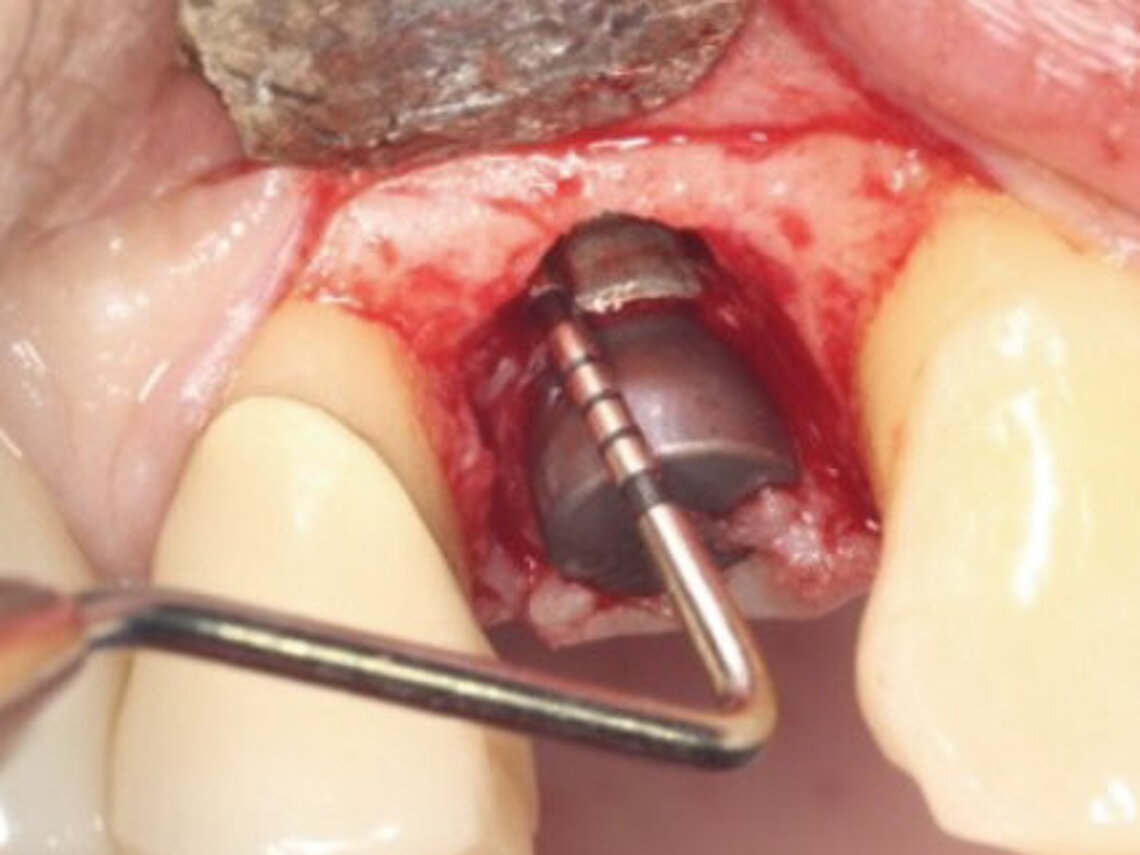

Peri-implant mucositis can be defined as an inflammatory lesion of the soft tissues (mucosa) surrounding the dental implant. Peri-implantitis is an inflammatory lesion of the mucosa affecting the supporting bone (crestal bone) with crestal bone loss and loss of osseointegration. Derks et al. report a prevalence of 43% for peri-implant mucositis and Jepsen et al. estimate that the prevalence of peri-implantitis could reach 22% (Figs. 1, 2).2,3 Peri-implantitis is usually accompanied by crestal bone loss (Fig. 3) and soft tissue changes in the peri-implant sulcus, which can be diagnosed by an increase in bleeding on probing (BOP) more than 5mm over previous examinations and/or suppuration8 (Fig. 4). Also excess of residual cement might contribute to crestal bone loss (Fig. 5).7